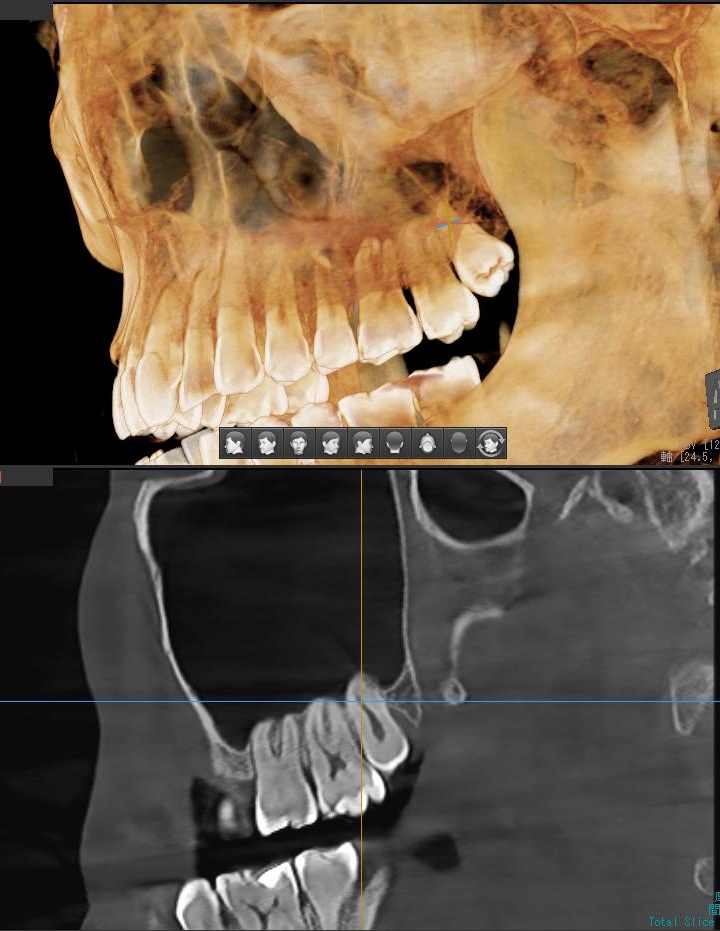

上顎の親知らずの場合、親知らずの根っこが上顎洞という空洞と非常に近い場合もあるため、CT撮影でも確認します。

今回は上顎洞から充分に距離があるため、抜歯は可能と診断されました。